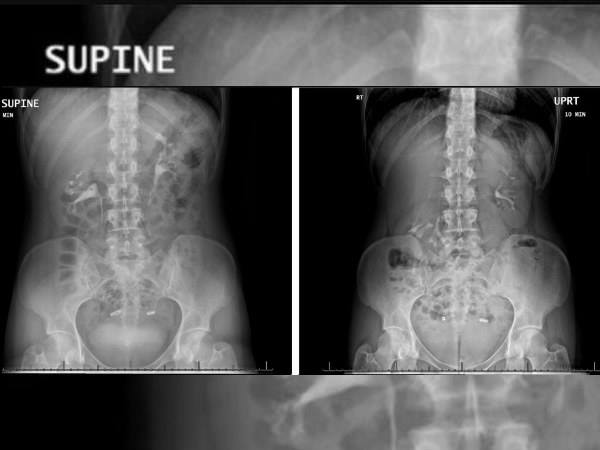

మొదటగా వైద్యులు ఆ మహిళను పరీక్షించినప్పుడు , ఏ విధమైన ఆలోచనలను చేయలేకపోయారు. అనగా దీని చికిత్సా విధానం కూడా అర్ధం కాలేదు. మామూలుగా ఉన్న వేళల్లో తీసిన స్కాన్ ప్రకారం కిడ్నీలు అవి ఉండవలసిన ప్రాంతంలోనే కనిపించేవి, కానీ ఆవిడ పూర్తిగా లేచి నిలబడి ఉన్న సమయంలో కుడివైపు కిడ్నీ పొత్తికడుపులోకి వెళ్ళినట్లు స్కానింగ్ లో కనిపించింది. తద్వారా కిడ్నీ పొత్తికడుపులోకి జారుతూ మరలా తిరిగి యదాస్థానానికి వస్తున్నట్లుగా వైద్యులు ధ్రువీకరించారు.

వైద్యుల ప్రకారం, కుడి వైపు కిడ్నీ కనీసం 2 ఇంచుల కిందకు జారడం జరిగింది. అనగా ఇంచుమించు 6 సెంటీమీటర్లు. తద్వారా ఆ మహిళ లేచినప్పుడు, పడుకున్నప్పుడు ఇతర అంతర్గత భాగాలకు తగలడం ద్వారా నొప్పి తీవ్రమయ్యేది. ముఖ్యంగా పడుకున్న తర్వాత పైకి లేయడం అత్యంత క్లిష్టమైన ప్రక్రియగా ఉండేది.